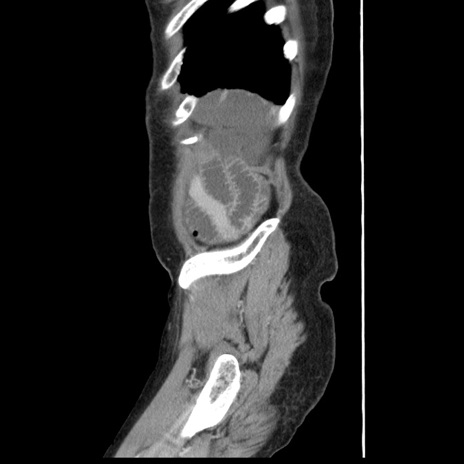

症例1(矢状断像)

【症例】80歳代女性

【主訴】腹痛

【現病歴】8時間前から腹痛あり来院。

【既往歴】糖尿病、脂質異常症、子宮体癌にて子宮全摘術

【身体所見】意識清明・会話良好だが腹痛で苦悶様、全腹部にわたって反跳痛と圧痛あり

【データ】WBC 13600、CRP 0.14、LDH 224、CK 90